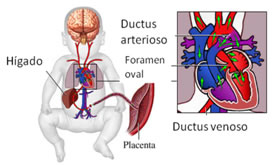

- El estudio Doppler del ductus venoso. El ductus venoso es el vaso que transporta la sangre de la placenta al corazón fetal; cuando la onda del flujo de este vaso es patológica permite sospechar la presencia de alguna alteración cromosómica.